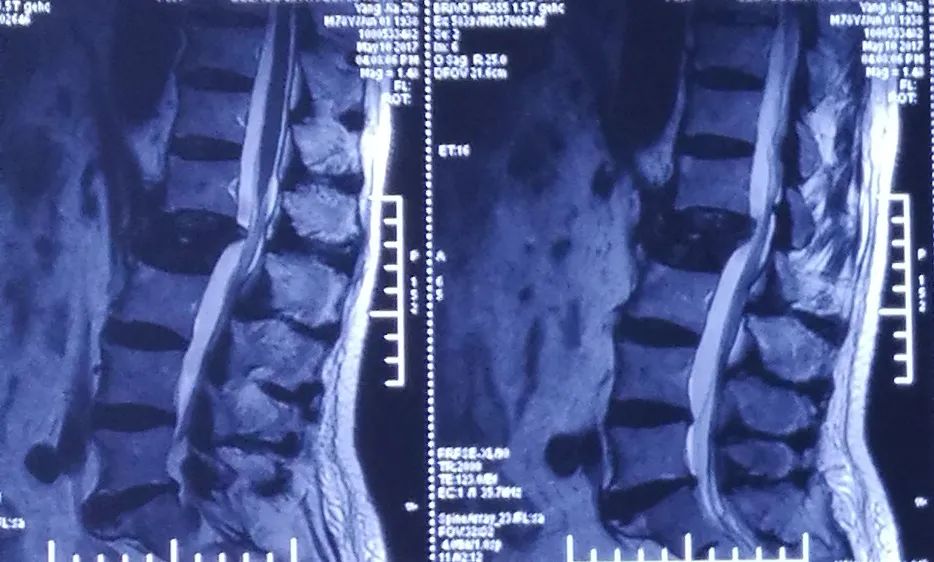

术前MRI

术后2周MRI

术前

术后2周